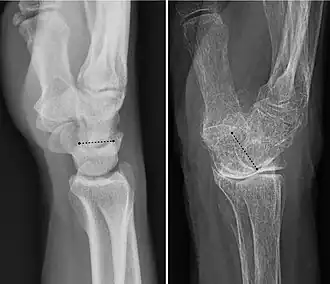

In human anatomy, the wrist is variously defined as (1) the carpus or carpal bones, the complex of eight bones forming the proximal skeletal segment of the hand;[1][2] (2) the wrist joint or radiocarpal joint, the joint between the radius and the carpus[2] and; (3) the anatomical region surrounding the carpus including the distal parts of the bones of the forearm and the proximal parts of the metacarpus or five metacarpal bones and the series of joints between these bones, thus referred to as wrist joints.[3][4] This region also includes the carpal tunnel, the anatomical snuff box, bracelet lines, the flexor retinaculum, and the extensor retinaculum.

As a consequence of these various definitions, fractures to the carpal bones are referred to as carpal fractures, while fractures such as distal radius fracture are often considered fractures to the wrist.

The radiocarpal (wrist) joint is an ellipsoid joint formed by the radius and the articular disc proximally and the proximal row of carpal bones distally. The carpal bones on the ulnar side only make intermittent contact with the proximal side — the triquetrum only makes contact during ulnar abduction. The capsule, lax and un-branched, is thin on the dorsal side and can contain synovial folds. The capsule is continuous with the midcarpal joint and strengthened by numerous ligaments, including the palmar and dorsal radiocarpal ligaments, and the ulnar and radial collateral ligaments. [6]

The parts forming the radiocarpal joint are the lower end of the radius and under surface of the articular disk above; and the scaphoid, lunate, and triquetral bones below. The articular surface of the radius and the undersurface of the articular disk form together with a transversely elliptical concave surface, the receiving cavity. The superior articular surfaces of the scaphoid, lunate, and triquetrum form a smooth convex surface, the condyle, which is received into the concavity.[7]